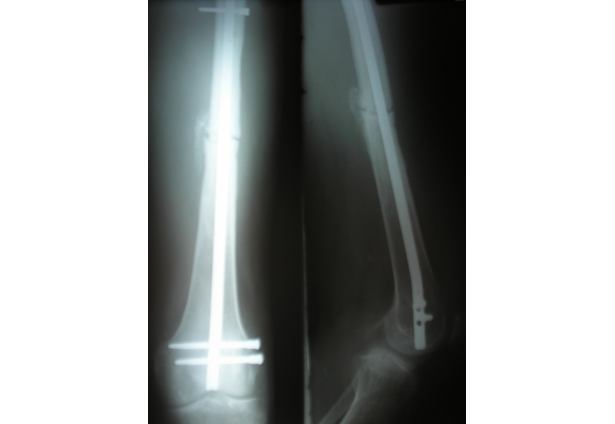

Our mission is to bring healing to the victims of orthopaedic injuries throughout the developing world. We collaborate with surgeons in these countries to develop orthopaedic implants and training that will help them to heal the severely broken bones of their patients. We manufacture and distribute these implants for free or at an affordable cost so that the working poor have an equal opportunity to receive modern effective orthopaedic treatment.